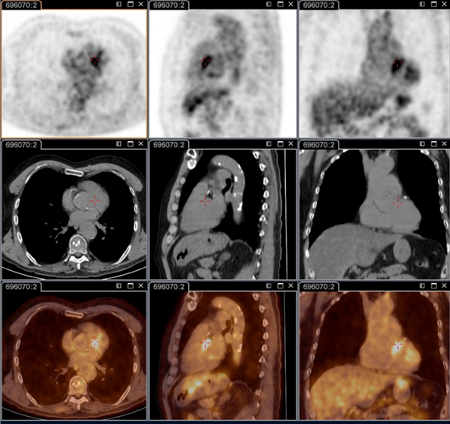

18F-fluorodeoxyglucose (FDG) PET/CT imaging

Test

Critical for identifying persistent focalised infections.[80]

Is able to decipher endocarditis, vascular infection, lymphadenitis, and osteoarticular infection; these conditions cannot be identified without this technique.

It is now part of the standard anatomical check-up in patients with persistent symptoms, and/or persistent elevated serology, and/or positive polymerase chain reaction on blood/serum, or any sample with clinical presentation not consistent with primary infection.[3]

It is specifically recommended for patients: with acute Q fever with persisting phase 1 IgG ≥1:800 and/or sign of bad evolution; with acute Q fever with a history of vascular graft or aneurysm; or with unexplained (phase 1 IgG ≥1:800) serology or clinical suspicion of a persistent infection.

Also useful for identifying infection in patients with vascular prosthesis and/or aneurysm, and identifying those who require surgery with resection of infected vascular tissues. [Figure caption and citation for the preceding image starts]: Q fever endocarditis diagnosed at PET scan: 18F-fluorodeoxyglucose PET/CT. In this asymptomatic patient with heart valve history with elevated serology, the PET scan diagnosed an aortic endocarditis on native valve with thoracic and lumbar aortic mycotic aneurysmsInstitut Hospitalo-Universitaire Méditerranée Infection (patient consent obtained) [Citation ends].

[Figure caption and citation for the preceding image starts]: Q fever aortic mycotic thoracic aneurysm diagnosed at PET scan: 18F-fluorodeoxyglucose PET/CT. In this asymptomatic patient with heart valve history with elevated serology, the PET scan diagnosed an aortic endocarditis on native valve with thoracic and lumbar aortic mycotic aneurysmsInstitut Hospitalo-Universitaire Méditerranée Infection (patient consent obtained) [Citation ends].